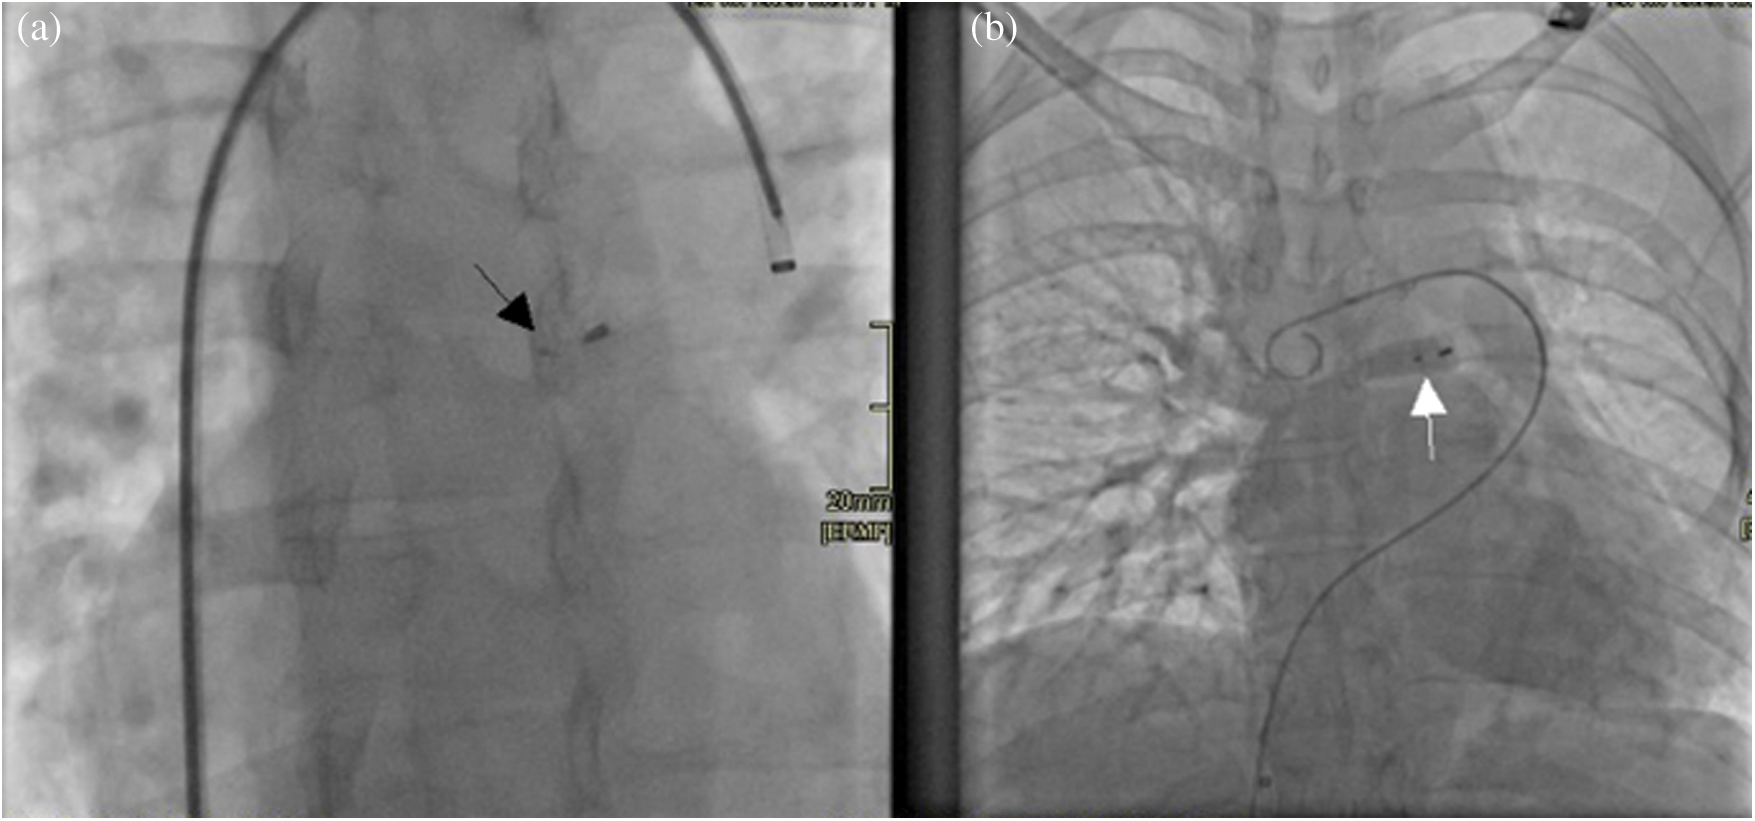

The procedure was performed under conscious sedation with right and left femoral veins access. After confirmation of anatomy using rotational angiography with live 3D reconstruction, the anomalous vein was cannulated using a 6F multipurpose diagnostic catheter. Subsequently, it was exchanged over an extra-stiff exchange wire for a 7‑Fr Shuttle carotid artery access system® (Cook, USA) which was positioned in the anomalous vein, close to the entering of the right pulmonary veins to the left atrium. The anomalous vein was then occluded deploying a 10 mm LepuMemopart vascular plug® (Lepu Medical, China). The occluding device size was selected to be approximately 50% larger than the target vessel. The final position of the device was above the drainage of the right‑sided pulmonary veins without impinging these structures. An angiography performed before device release from the right pulmonary artery using a Pig-tail catheter advanced through the additional femoral vein access, confirmed during levophase, the patency of the right pulmonary veins as well as total occlusion of the anomalous vein (Fig. 4). Redirection of blood flow from the right pulmonary veins to the left atrium was successfully achieved. Pulmonary artery pressure remained unchanged post occlusion. There were no complications.

Figure 4: (a) Radioscopy image obtained in an antero-posterior projection showing the vascular plug device in situ (black arrow). (b) A right pulmonary artery angiography shows during levophase, the three right pulmonary veins draining unobstructed into the left atrium after occlusion of the anomalous vein with a device (white arrow)